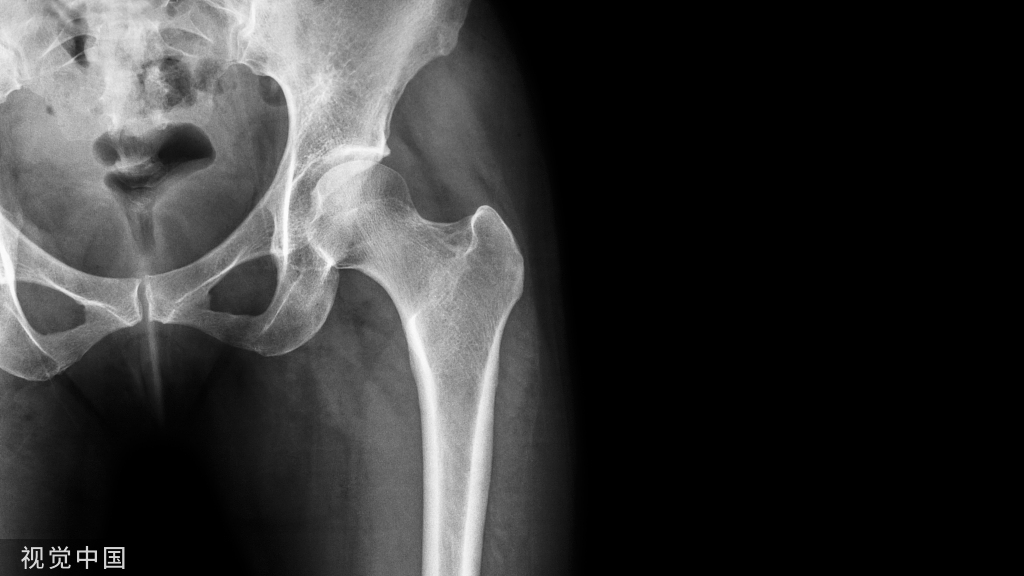

髋部特殊检查

髋关节屈曲孪缩试验:又称托马斯(Thomas)征。患者仰卧,将健侧髋膝关节尽量屈曲,大腿贴近腹壁,使腰部接触床面,以消除腰前凸增加的代偿作用。再让其伸直患侧下肢,若患肢随之跷起而不能伸直平放于床面,即为阳性征。说明该髋关节有屈曲挛缩畸形,并记录其屈曲畸形角度。

髋关节过伸试验:又称腰大肌孪缩试验。患者俯卧位,患侧膝关节屈曲90°,医生一手握其踝部将下肢提起,使髋关节过伸。若骨盆亦随之抬起.即为阳性征。说明髋关节不能过伸。腰大肌脓肿及早期髋关节结核可有此体征。

单腿独立试验:又称屈德伦堡(Trendeienburg)征。此试验是检查髋关节承重机能。先让患者健侧下肢单腿独立,患侧腿抬起,患侧臀邹襞(骨盆)上升为阴性。再让患侧下肢单腿独立,健侧腿抬高,则可见健侧臀皱襞(骨盆)下降,为阳性征。表明持重侧的髋关节不稳或臀中、小肌无力。任何使臀中肌无力的疾病均可出现阳性征。

下肢短缩试验:又称艾利斯(Allis)征。患者仰卧,双侧髋、膝关节屈曲,足  跟平放于床面上,正常两侧膝顶点等高、若一侧较另一侧低即为阳性征。表明股骨或胫腓骨短缩或髋关节脱位。

望远镜试验:又称套迭征。患者仰卧位,医生一手固定骨盆,另一手握患侧腘窝部,使髋关节稍屈曲,将大腿纵向上下推拉,若患肢有上下移动感即为阳性征。表明髋关节不稳或有脱位,常用于小儿髋关节先天性脱位的检查。

蛙式试验:患儿仰卧,将双侧髋膝关节屈曲90°位,再作双髋外展外旋动作,呈蛀式位。若一侧或双侧大腿不能平落于床面,即为阳性征,表明髋关节外展受限。用于小儿先天性髋脱位的检查。

股骨头大粗隆位置的测量

内拉通(Nelaton)线:又称髂坐结节联线。患者仰卧位,髋关节屈曲45-60°,由髂前上棘至坐骨结节划一联线,正常时此线通过大粗隆顶部。若大粗隆顶部在该线的上方或下方,都表明有病理变化。

布来安三角:患者仰卧位,自髂前上棘与床面作一垂线,自大粗隆顶点与垂直线作一水平线,再自髂前上棘与大租隆顶点之间连一直线,构成一直角三角形。对比两侧三角形的底边长度,若一侧变短,表明该侧大租隆向上移位。

休梅克(Shoemarker)线:患者仰卧位,双下肢伸直于中立位,两侧髂前上棘在一平面,从两侧髂前上棘与大粗隆顶点分别连一直线,正常时两线延长交于脐或脐上中线。若一侧大粗隆上移.则延长线相交于脐下且偏离中线。